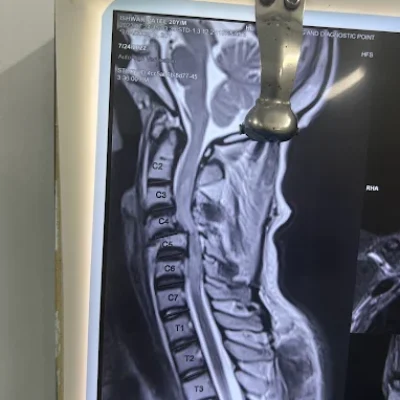

- High-resolution MRI & CT scans for detailed brain and spine imaging